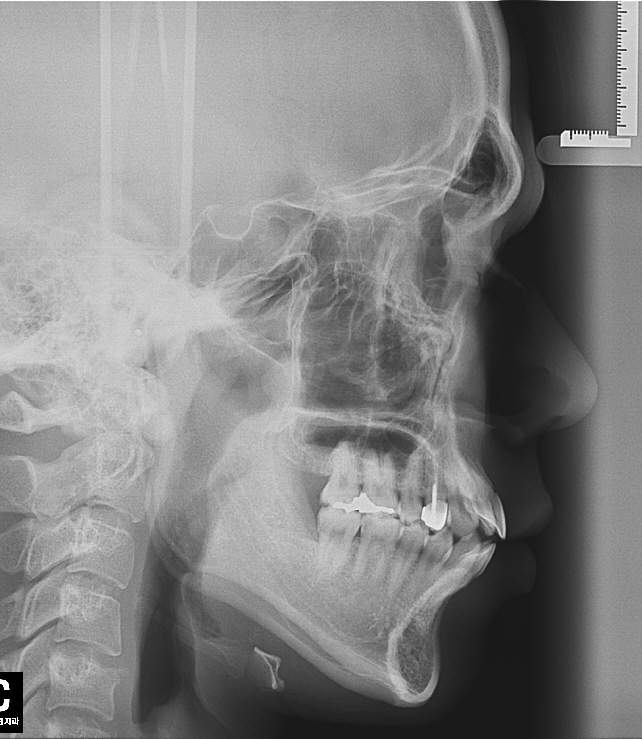

사진은 제 치아상태입니다. 좋은말씀부탁드립니다

네.... 인비절라인은 본뜬 모델에서 먼저 치아를 이동하여 제작한 틀을 껴서 치아를 이동하는 방식이랍니다. 비교적 적은 치아이동이 이뤄지는 배열은 여러가지 장점을 가지고 있지만 님의 경우와 같이 발치교정을 하는 경우는 많은 치아의 이동이 필요하기 때문에 치아에 부착하는 브라켓 장치에 비하여 정밀도가 떨어지는 것은 사실이랍니다. 인비절 라인 장치와 함께 여러가지 보조적인 장치를 같이 사용하여 진행하기도 하지만 전반적인 부분을 고려할때 일반적인 부착형 교정장치를 사용하는 것이 좋을 것 같습니다...^^